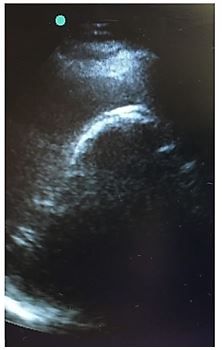

Patient history. A man in his sixties with a history of diabetes and hypertension presents to the emergency department with acute onset of epigastric pain at 5 am associated with chills and nausea. He denies fever or shortness of breath, vomiting, diarrhea, dysuria, or flank pain. He does not volunteer it, but when asked specifically does admit discomfort in the area of the right scapula.

What does the case image show?

Cholecystitis fromThe Emergency Medicine 1-Minute Consult Pocketbook